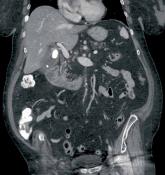

ArticleEpigastric abdominal painAuthor:Keith D. Hentel MdPublish date: January 24, 2014 An 83-year-old man with a history of hypertension, hyperlipidemia, coronaryartery disease, and gastroesophageal reflux disease presents to the ED ...Read More